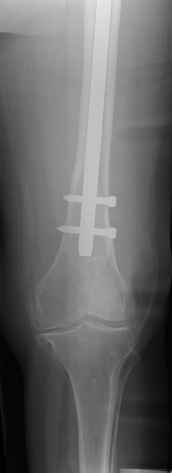

4. We could treat this fracture like there is no a nail - new locking plates allow for secure fixation.... two similar cases are attached...

Images sent by Professor Kanlic look nice, very good job. Excellent achorage in distal fragment. However, unicortical screwing or bicortical

makes a difference, also for locked screws. Proximal fragment unicortical fixation may present stability not easlily predictable. Certainly its stability for wheelchair should be sufficient. Full weight bearing can not be mentioned for this case. If minimal bearing is allowed full weight

Images sent by Professor Kanlic look nice, very good job. Excellent achorage in distal fragment. However, unicortical screwing or bicortical makes a difference, also for locked screws. Proximal fragment unicortical fixation may present stability not easlily predictable. Certainly its

stability for wheelchair should be sufficient. Full weight bearing can not be mentioned for this case. If minimal bearing is allowed full weight